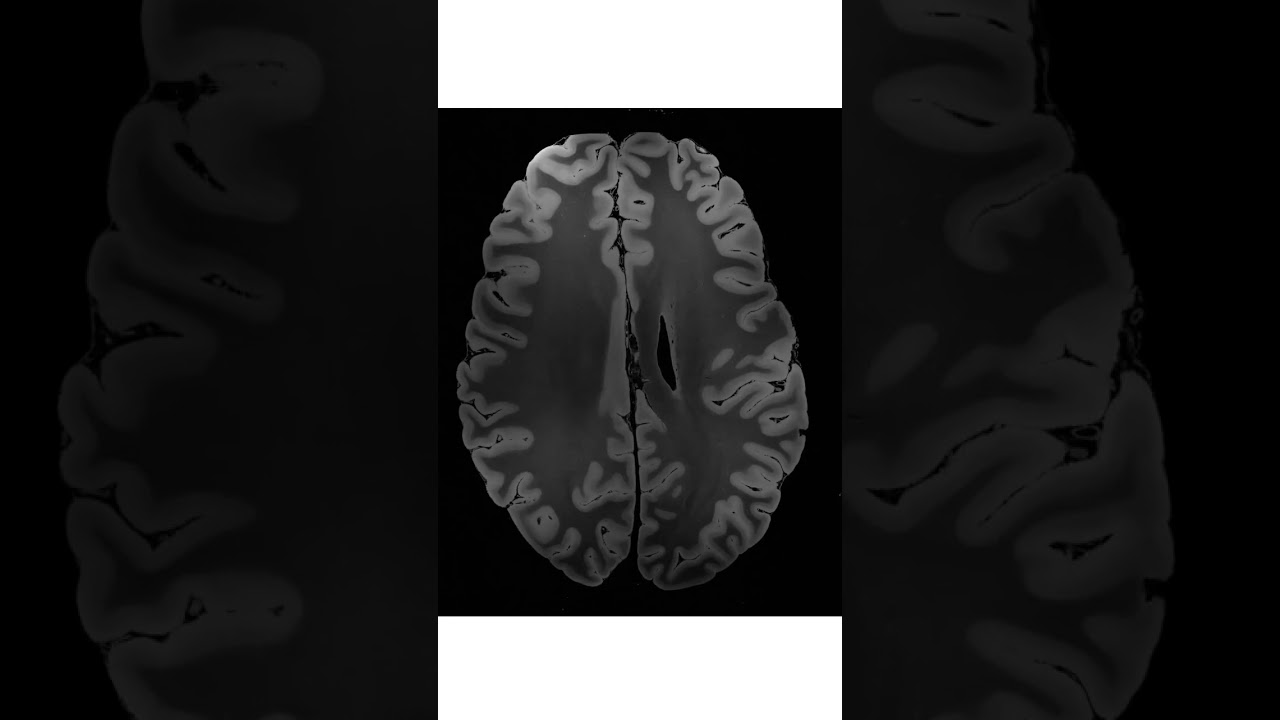

7 Tesla MRI dataset of an ex vivo Human Brain Specimen 😮😮

Healthcare Medicine AI